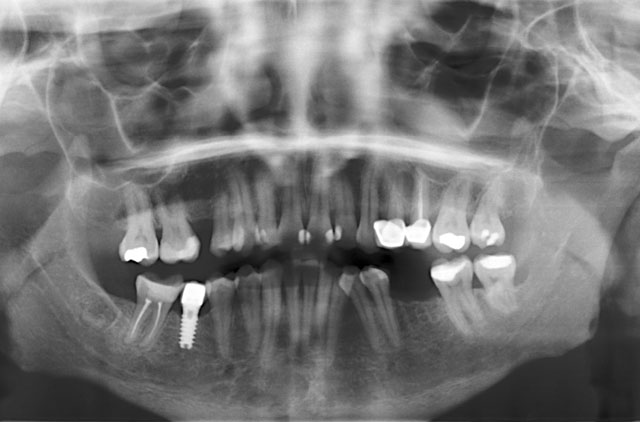

RADIOGRAFÍA

-Panorámica (OP)

-Panorámica (OP) con 1.25 de Magnificación para implantes

-Panorámica Región Dientes Anteriores

-Panorámica Región Derecha

-Panorámica Región Izquierda